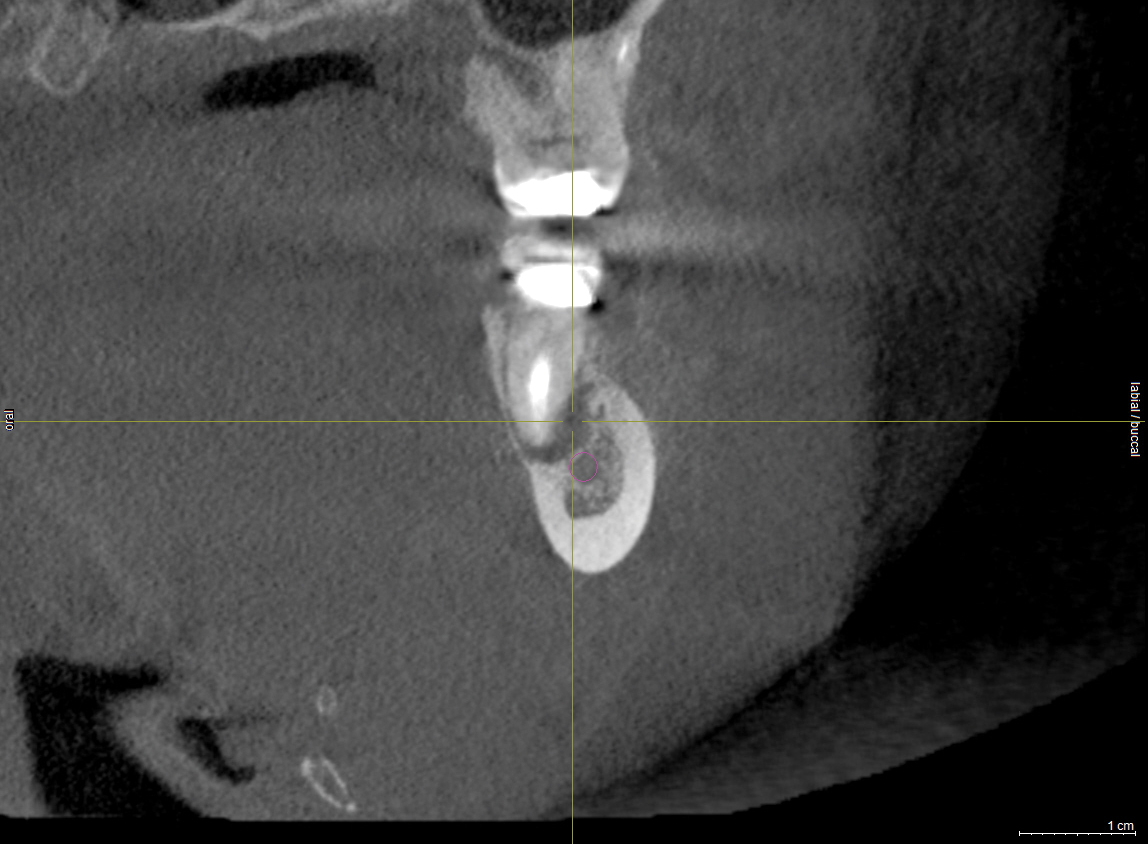

Subsequent to nerve injury, the clinician needs to determine if immediate referral is necessary or a pharmacologic approach is warranted or if implant removal or reverse-torquing it a little would best serve a patient. There are diverse opinions in the literature pertaining to when and under what conditions referral to a microsurgeon is needed.58,59 It is generally agreed that if a clinician believes that a nerve has been transected as a result of an implant procedure, immediate referral is warranted.12,51,54,60,61 On the other hand, if a patient manifests neurologic symptoms post-implantation, but the clinician is sure that the drill never entered the mandibular canal, it is possible that postoperative altered sensation is caused by traction of a nerve or an inflammatory process. Then a pharmacologic approach may be warranted.3 A clinician can be almost sure that the drill did not enter the mandibular or mental canal if after each drill, the floor of the osteotomy was checked with an implant probe or if a radiograph clearly depicts the osteotomy terminated several millimeters from the nerve canal. The previous remark is qualified, because there is the remote possibility that some unusual branch of the IAN was present and damaged. From another perspective, a CBCT scan can be ordered to attain an enhanced view of the implant’s relationship to vital structures if a 2-dimensional radiograph was initially used to assess the situation (Figure 1 and Figure 2).

Fig 2. The implant restoration was completed 10 years ago and the patient has been able to accommodate the altered nerve sensation. Recently, the patient presented at one of the authors’ offices and a CBCT scan was ordered. It demonstrated that the implant at site No. 30 is closer to the inferior alveolar canal than previously envisioned and may be causing compression on the nerve.

Figure 2